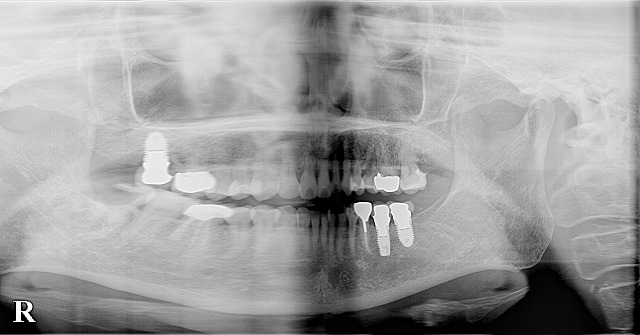

審美歯科 ねじ穴の見えたインプラントの交換 2021.08.11 LINE note Post Share Hatena LINE RSS feedly Pin it note この記事のタイトルとURLをコピーする 透明マウスピース矯正によるクロスバイト(交叉咬合)の治療 前の記事 矯正治療と虫歯治療とインプラント治療の長期経過 次の記事